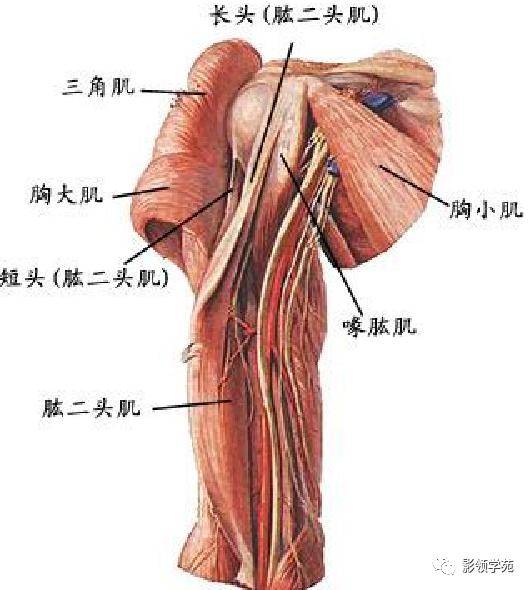

手臂动脉走向

手臂动脉走向